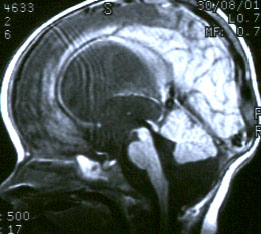

Медицинская диагностика: Супраселлярная арахноидальная киста